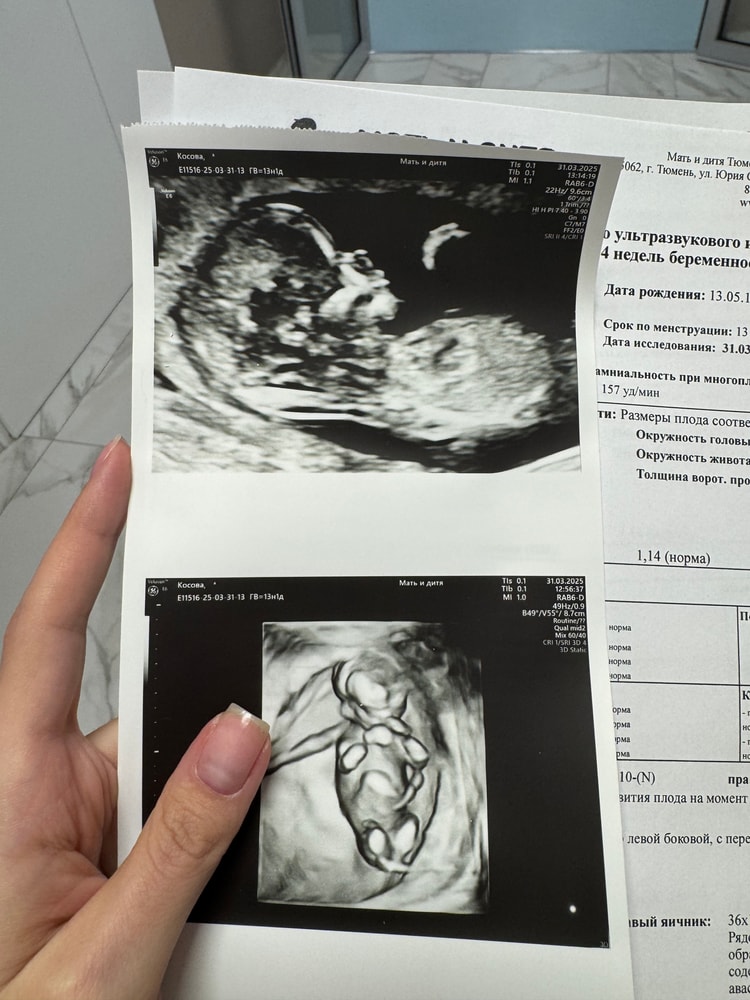

1 скрининг

Скрининг.. у нас был в 13.1 недель. Такое классное часовое УЗИ со всеми подробностями! Невероятные эмоции от осознания, что вот он человек. А еще несколько месяцев назад это казалось несбыточной мечтой

Прикрепила фото. Ну и классическое, на кого похож ? ☺️🩷🩵